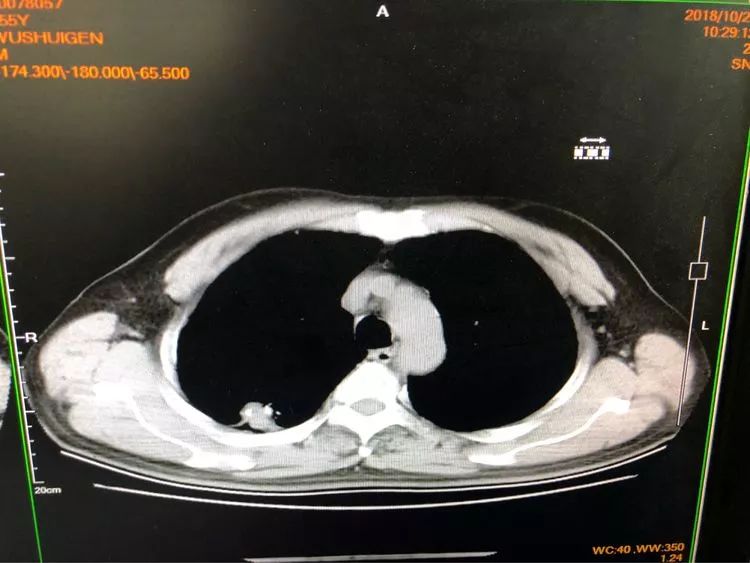

第三例 吳大伯今年55歲,右上肺后段結節(jié)樣病變,伴有鈣化,一般這種情況大家都會覺得是結核球。

由于患者門診抗結核治療病灶稍增大,醫(yī)生們經(jīng)商議最終決定穿刺。雖然從影像看起來沒有穿刺路徑,不過沒關系,省胸科醫(yī)院經(jīng)驗豐富的內(nèi)科醫(yī)生們可以通過體位來調整。